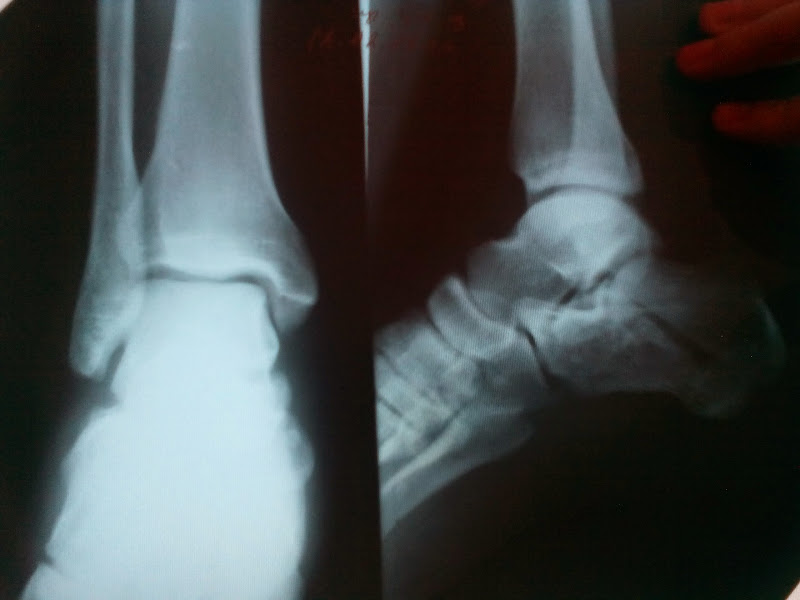

Добрый вечер. Помогите мне с снимком. У нас травматолога нет. Упал с туры на одну ногу. Что именно сломано и есть ли смещения? Спасибо!

Консультирует Москальченко Андрей Михайлович, врач-травматолог клиники «Медицина»: "Добрый вечер! Скажу сразу про снимки — качество и количество, недостаточное для точного диагноза. Имеет место перелом тела пяточной кости со смещением, но смещение расценивается в данном случае как допустимое. Для полноты картины необходим аксиальный снимок пяточной кости, для оценки смещения во фронтальной плоскости. Нужна очная консультация врача-травматолога".